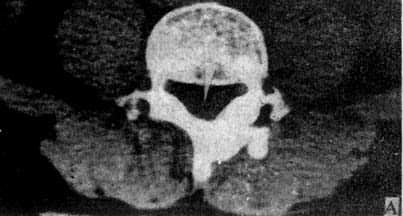

1.椎弓根层面 由椎体、椎弓根、椎弓板棘突围成一完整的骨环称为椎管(图5-1-5A)。正常椎管前后径为16~17mm,下限11.5mm;横径20~24mm,下限16mm。

A.椎弓根层面显示椎管由椎体、椎弓根和椎弓板围成的骨环,椎管中央为脊髓(→)